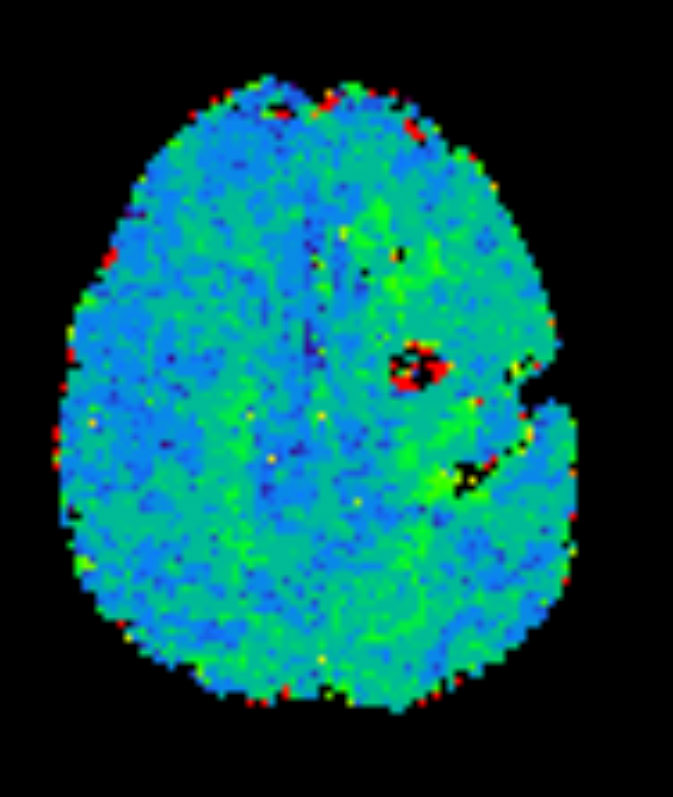

Axial T2* Perfusion - rCBF